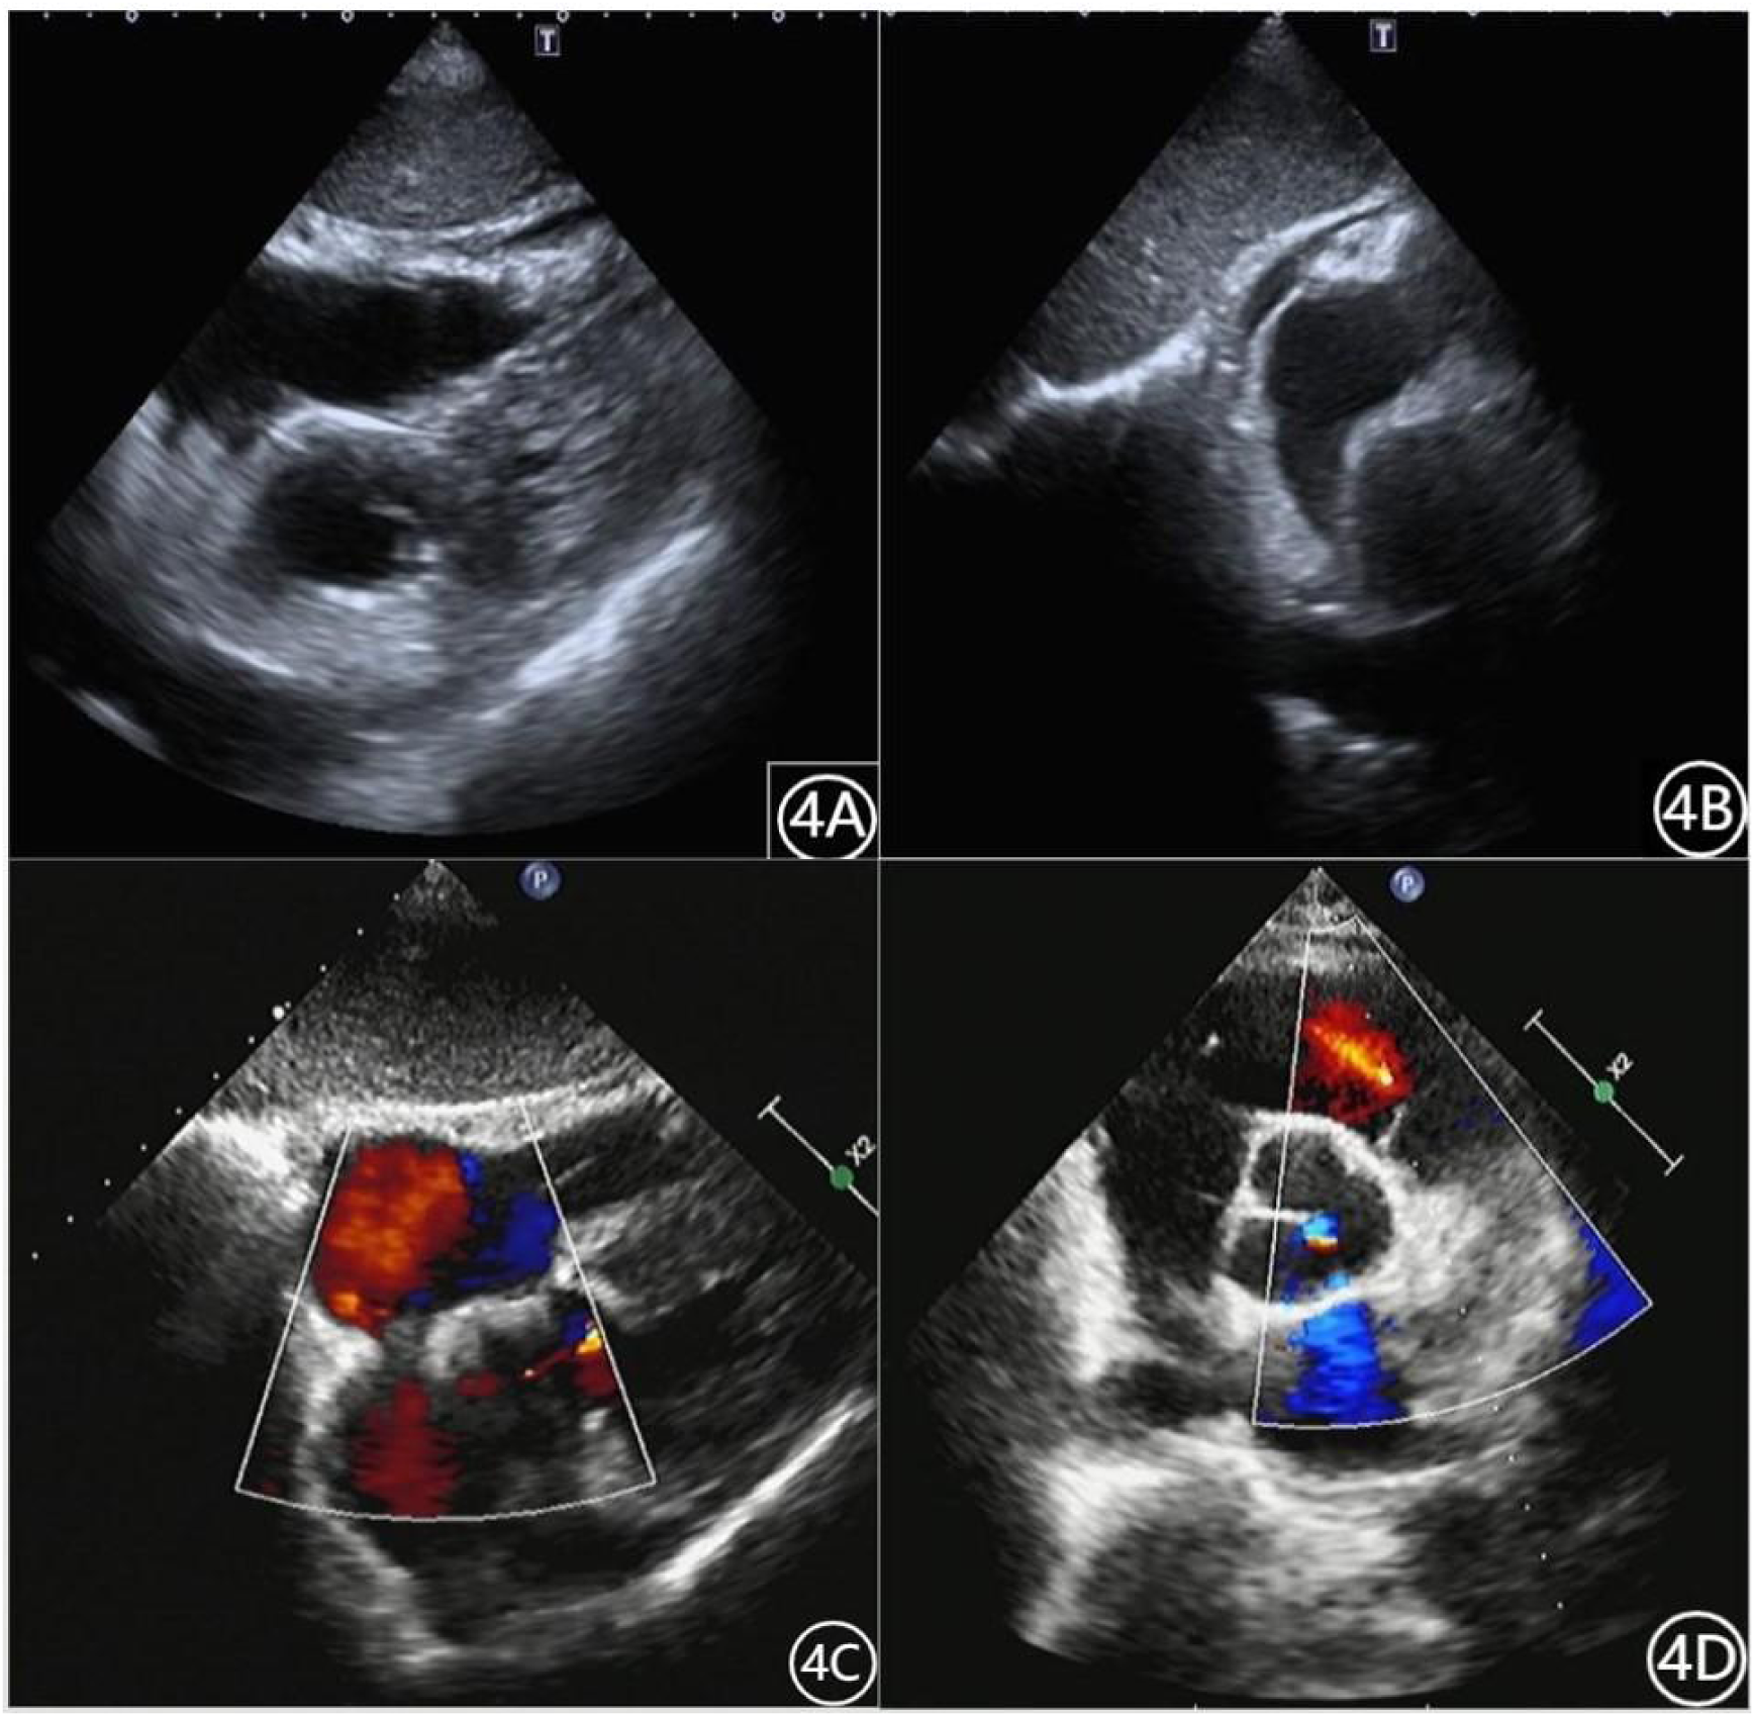

On the third (Figure 4A) and eighth (Figure 4B) days of hospitalization, echocardiography showed minimal pericardial effusion and no pericardial masses. During the remainder of the hospital stay, the patient experienced no chest pain or palpitations and was discharged after removal of the drainage tube. Follow-up echocardiography on day 7 (Figure 4C), day 18 (June 18, outside hospital), and day 38 (Figure 4D) showed no significant pericardial effusion, and the patient reported no complaints during daily activities.

Figure 4

Patient's cardiac ultrasound data (A): May 23, 2022. (B): May 28, 2022. (C): June 6, 2022. (D): July 8, 2022.